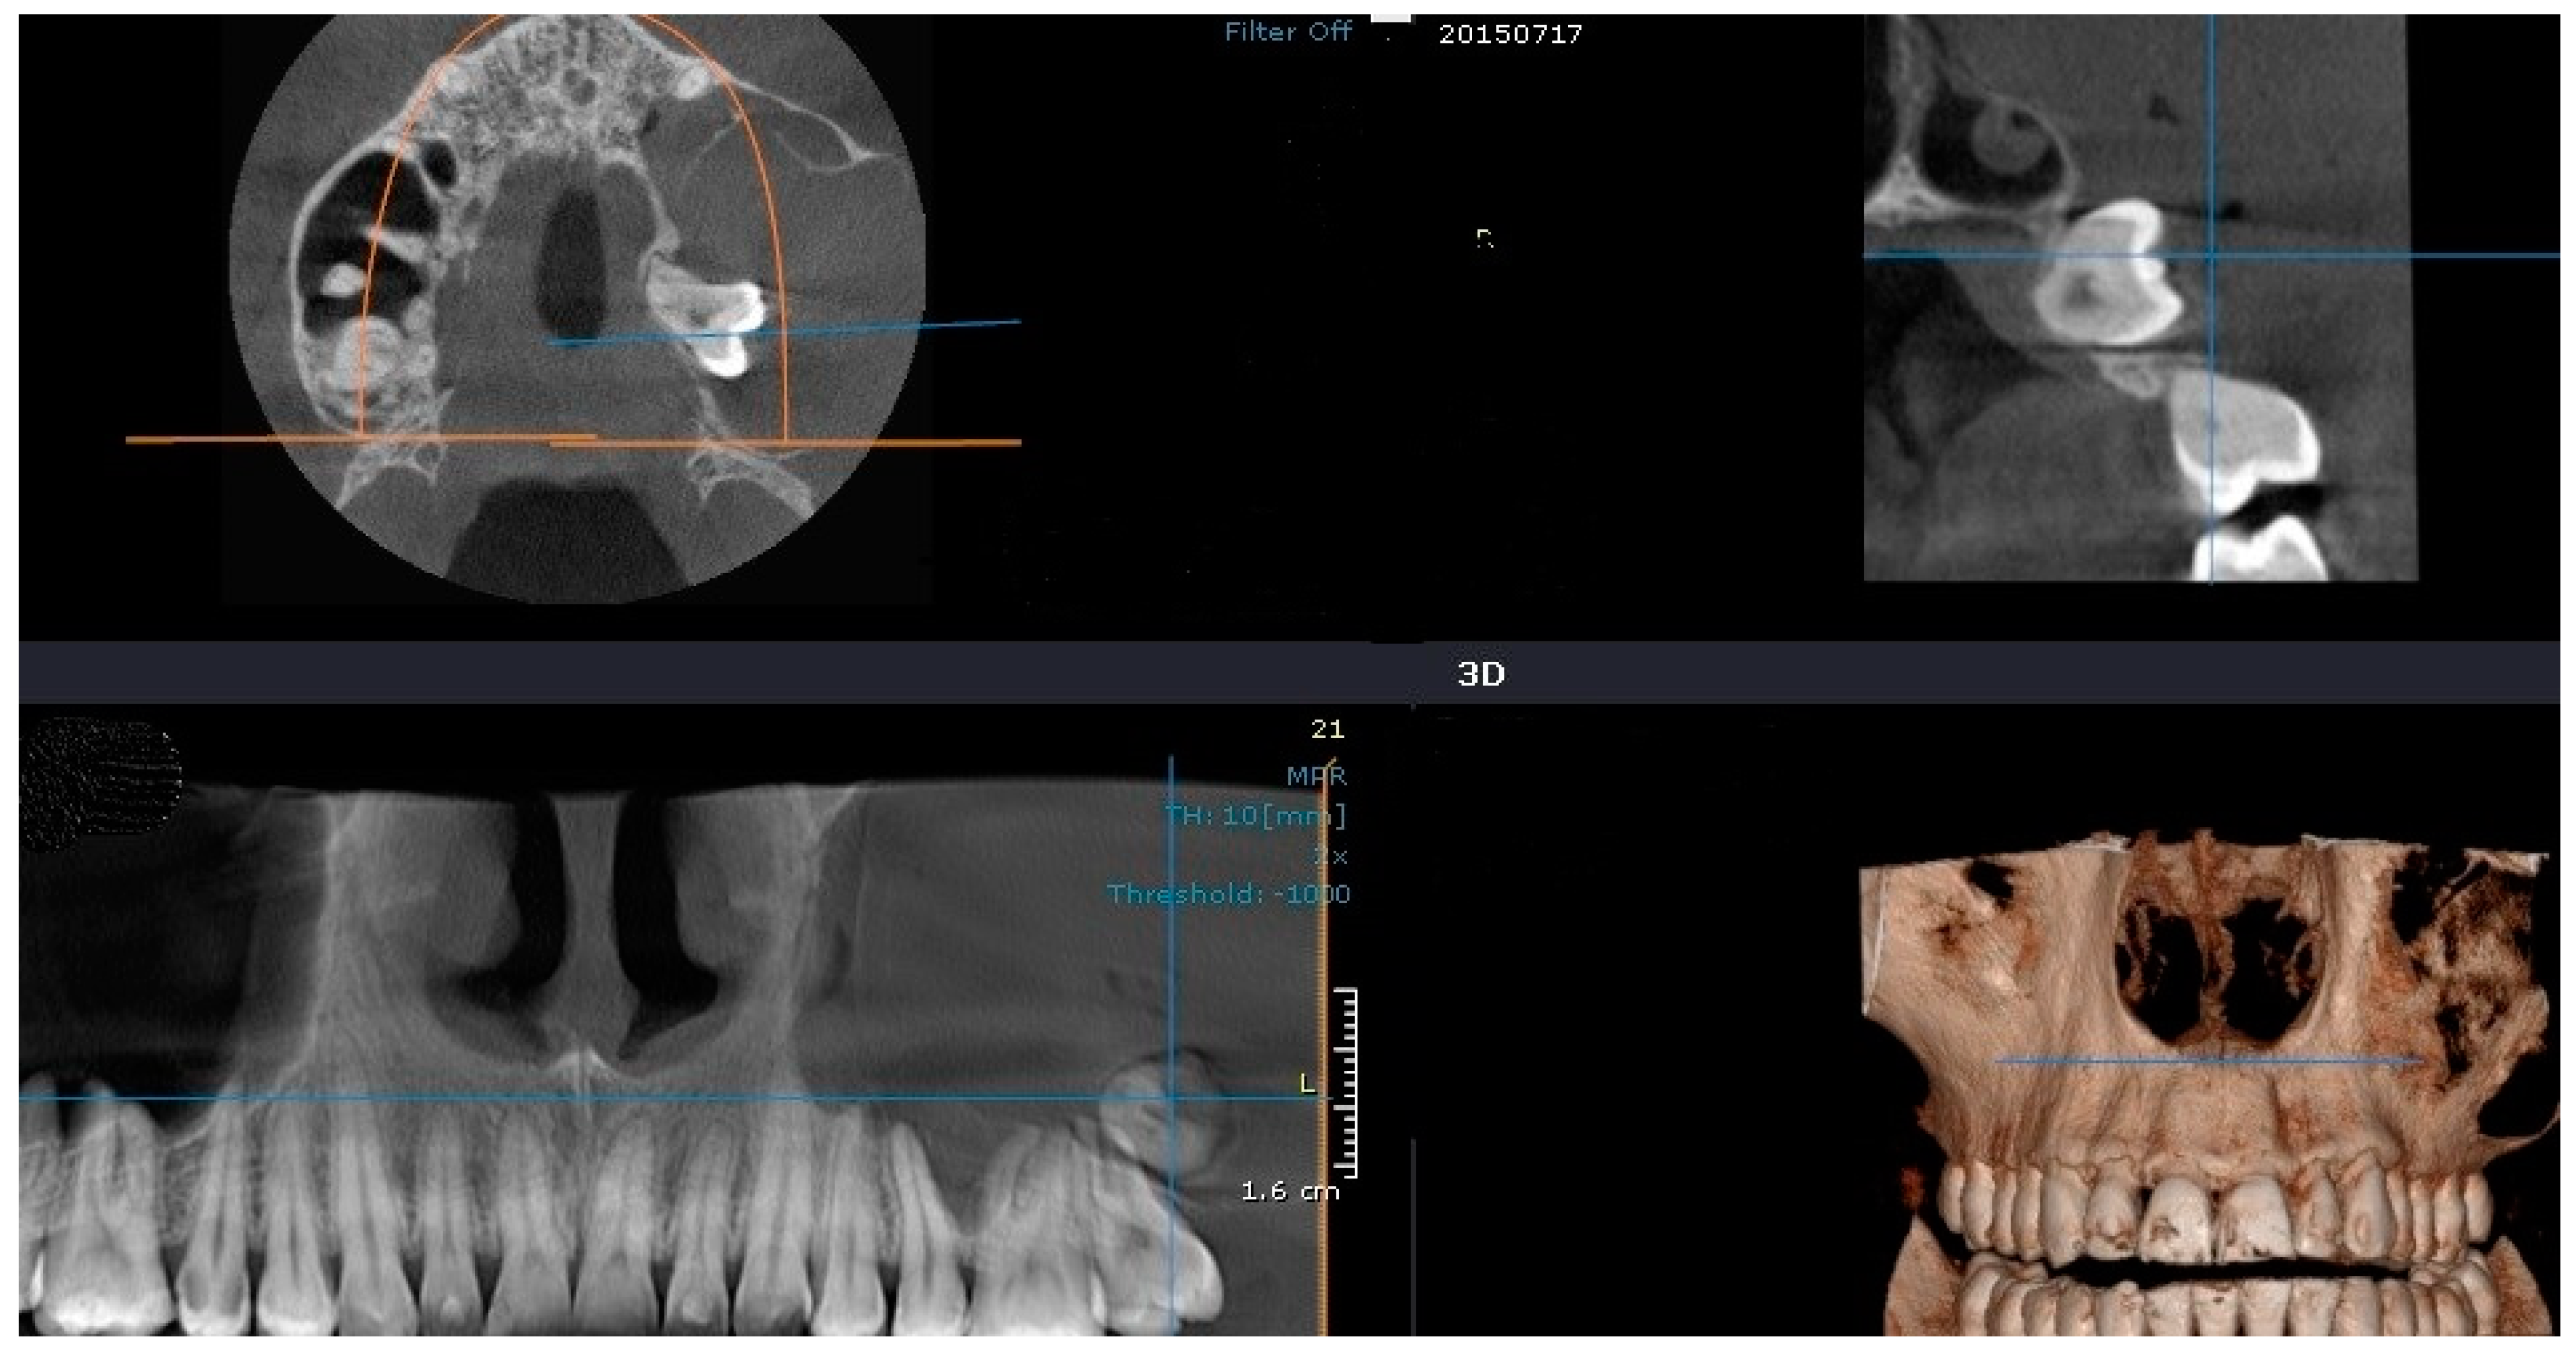

2.2.3. Case 3